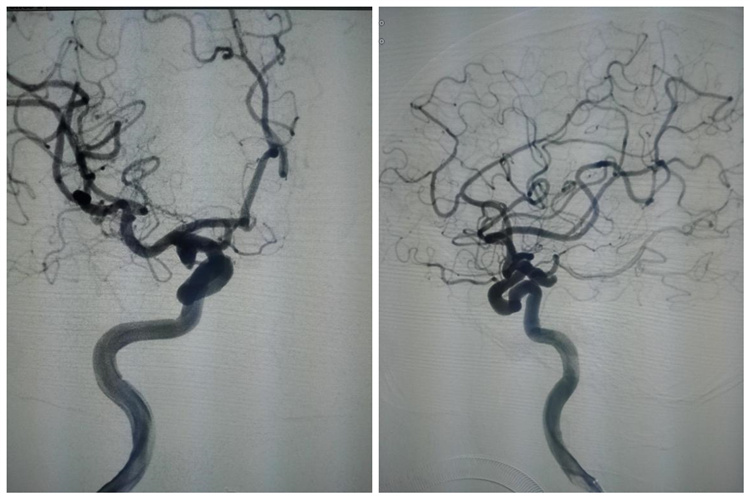

术前造影(右侧后交通动脉瘤):

.jpg)

栓塞术后造影:

.png)